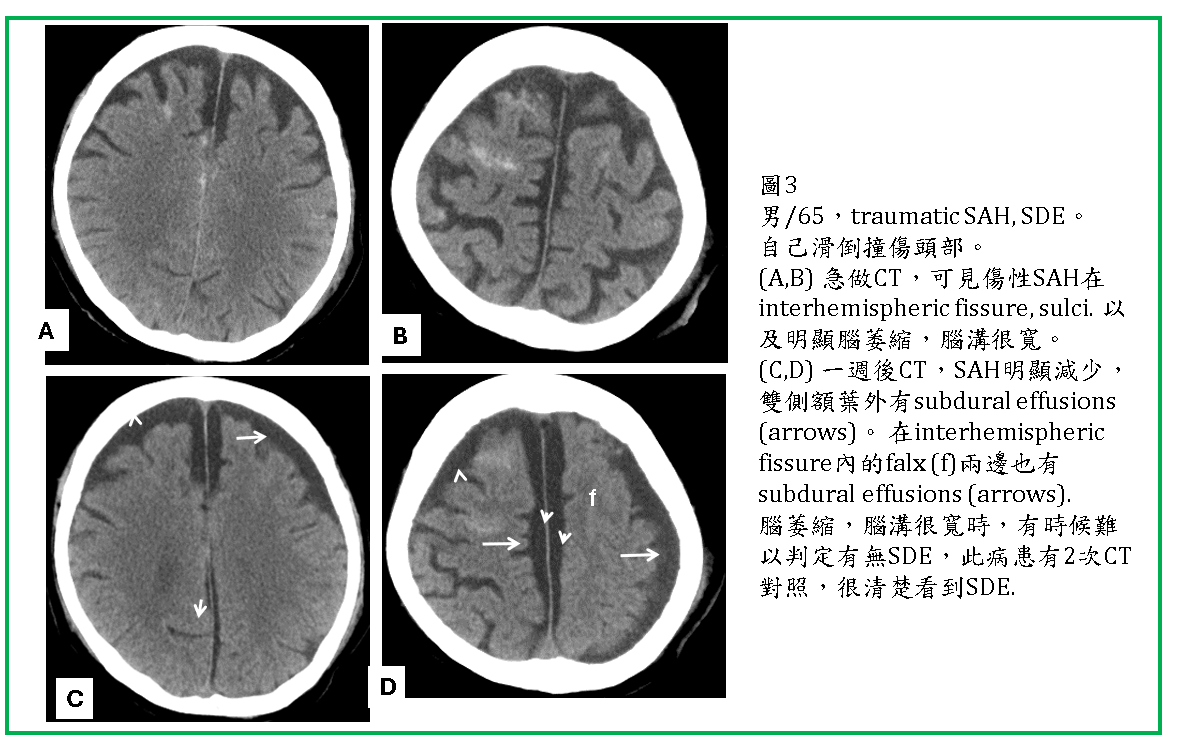

外傷後數天SDE才逐漸形成,而且通常都是雙側性的(圖1,2,3) 。有些是急性subdural hematoma沒處理,血塊逐漸演變成subdural effusion.

SDE通常位於大腦額頂葉外(圖1,2,3,4) ,有時也會在後顱窩,小腦天幕(tentorium)邊,及大腦鐮(falx)邊(圖3)。

SDE可能會再出血,形成SDE混合SDH(圖2) ,或逐漸形成 chronic subdural hematoma (CSDH) (圖4) .